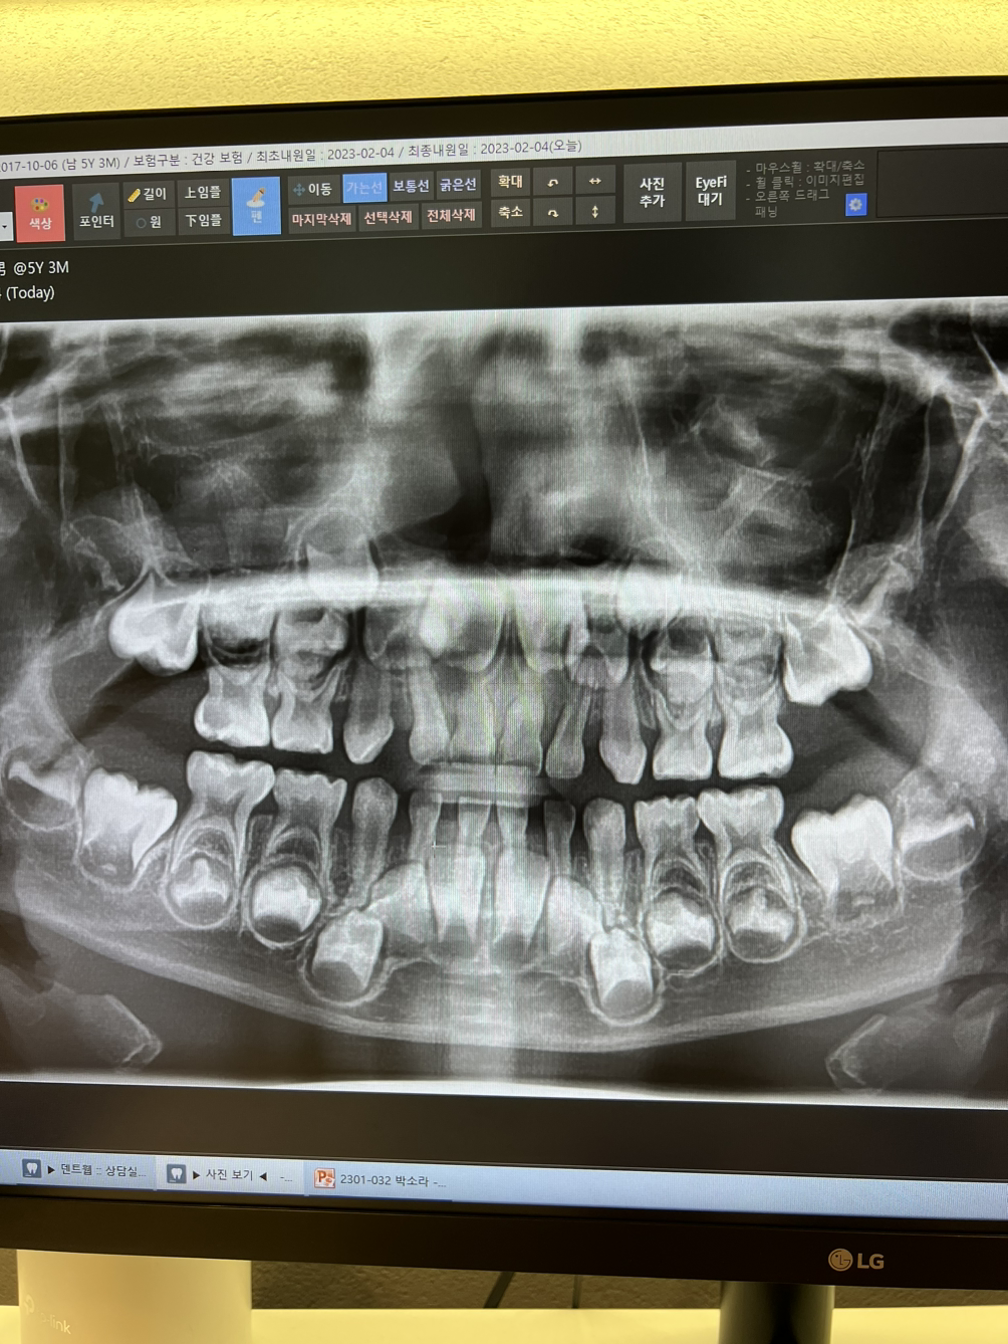

가고자 하는 지역의 학교가 정해졌다면 해당 학교에서 원하는 서류를 안내에 따라 준비해야 한다. 일반적으로는 영문 예방접종 기록과 TB검사 테스트라 불리는 결핵 피부반응 검사(tuberculin skin test)서 제출을 요구하는데 학교에 따라 영문 구강 검진 기록을 요구하는 경우도 있다. 요구사항이 학교마다 조금씩 다르고 산호세 일부 학교의 경우 캘리포니아주 의사면허 소지자의 도장이 찍힌 서류만 인정하는 곳도 있다고 하는데 외국인 학생의 경우 해당 국가에서 발급한 서류도 허용하는 경우가 있기 때문에 사전에 반드시 지원하는 학교에 이메일 문의를 하고 피드백을 받는 것이 중요하다. 미국뿐 만 아니라 선진국이라 불리는 독일, 영국 해외 어느 나라를 가도 한국처럼 예약 없이 병원을 방문해도 바로 진료를 받을 수 있게 해 주는 병원을 찾기 쉽지 않다. 더구나 한 번이라도 미국에서 소아과를 방문해 본다면 한국에서 받던 의료서비스와 보험 혜택이 얼마나 우수하고 신속하게 처리해 주는 것인지 알 수 있을 것이다. 한국에서 TB테스트를 진행하는 병원은 관할 보건소에 문의하면 안내해 준다. 참고로 이곳 산호세에선 TB테스트만 120~135$을 받는다. 그것도 예약 필수에 결과서는 10일 이후에나 받을 수 있고 한국에서 5만 원이면(병원마다 다를 수 있음) 받을 수 있는 영문 구강 검진 결과서는 200$~300$의 고 비용을 지불해야 한다. 그러니 반드시 학교에 사전 문의하여 한국 병원에서 발급한 서류도 가능한지 여부를 피드백을 받으면 불필요한 시간과 비용에 더해진 감정 소비를 줄일 수 있다.

미국으로 오기 한 달 전, 아이 유치원 친구 아빠가 계신 치과에 놀러 갔다 충치를 4개나 발견하고 부랴부랴 충치 치료를 출발 전 주까지 마치고 왔다. 특히 윗 쪽 어금니의 경우 신경 근처까지 썩어 그때 발견하지 못했다면 지금 이곳에서 고생스레 치과를 다녔을지 모를 일이다. 미국에선 마취비용도 모두 따로 추가 결재해야 하는데 웃음 가스 비용만 75$, 마취 주사는 200$정도로 한국과는 비교할 수 없을 만큼 진료 비용이 높다. 여행자 보험 중, 치과 치료가 커버 가능 한 보험도 있는 것으로 알고 있지만, 되도록 한국에서 치료받고 오는 것이 엄마와 아이 모두에게 편한 길이다.

리온치과 교정과 치과의원